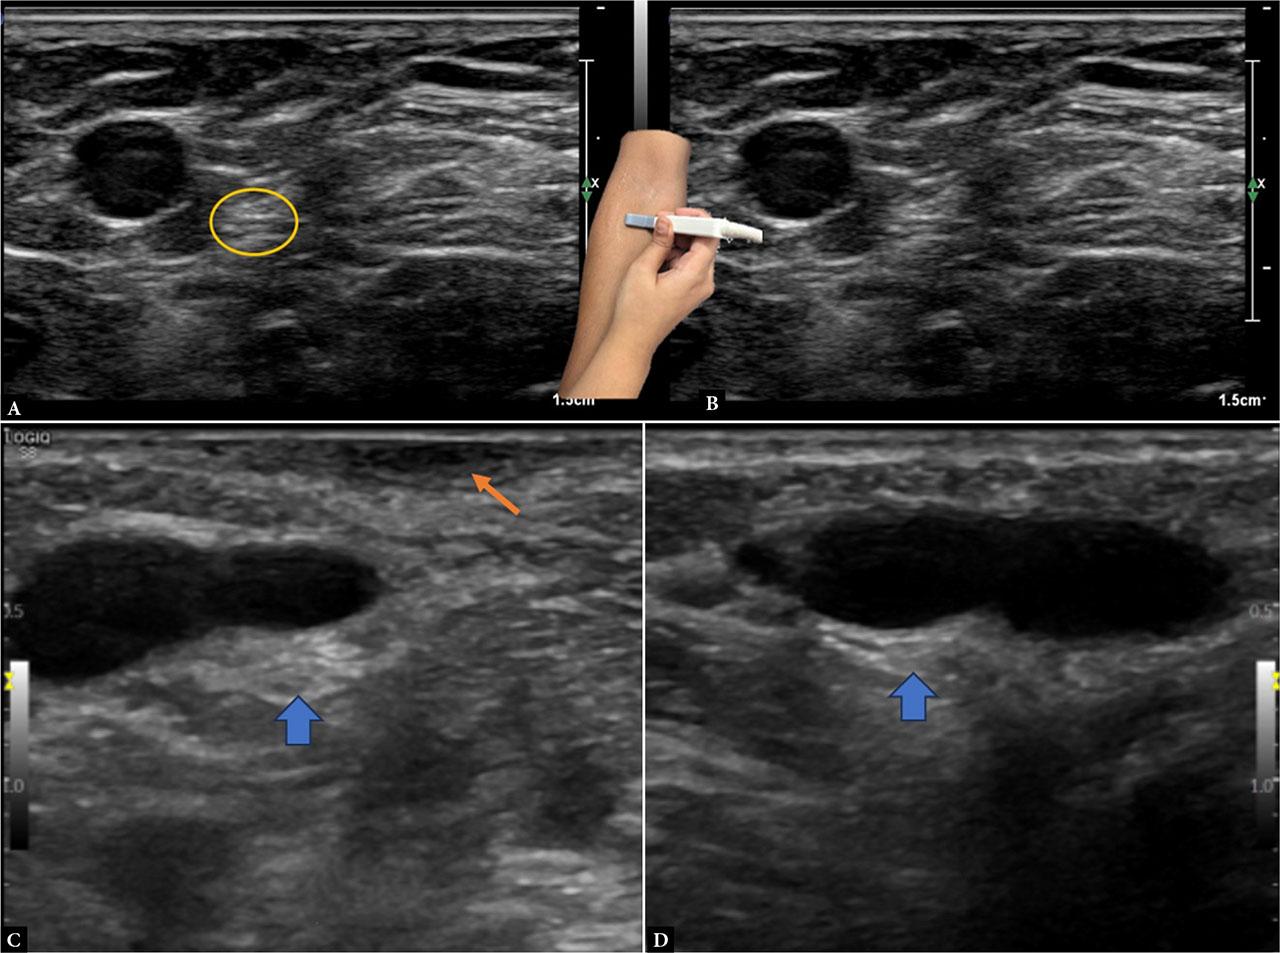

The lateral antebrachial cutaneous nerve (LABCN), the terminal branch of the musculocutaneous nerve, is readily imaged with high-frequency sonography near the elbow crease. Positioned lateral to the biceps tendon and adjacent to the cephalic vein, the nerve can be visualized in the short-axis view. The cephalic vein, easily identified with minimal transducer pressure, serves as a landmark and helps trace the nerve’s origin from the musculocutaneous nerve within the biceps muscle using a linear probe (15–18 MHz) with the patient supine and the elbow slightly flexed. With the probe placed at the elbow crease, the biceps tendon is seen centrally and the brachial artery medially. The LABCN lies lateral to the biceps tendon, then courses subcutaneously along the radial aspect of the forearm(10) (Fig. 4).

The lateral antebrachial cutaneous nerve (yellow circle) is identified in the antecubital fossa, adjacent to the cephalic vein (A and B). Note probe position in the inset. Image C demonstrates thickening of the LABC (blue arrow) in a patient following biceps tendon repair, compared to the contralateral normal nerve in image D. The orange arrow demonstrates focal scarring of the overlying skin in image C, indicating prior surgical intervention

Injuries most frequently arise from venipuncture or distal biceps tendon tears. Sonographically, the nerve may appear enlarged or hypoechoic with altered echotexture. Dynamic imaging during forearm rotation (supination/pronation) can reveal entrapment by tendon during movement (Fig. 4).